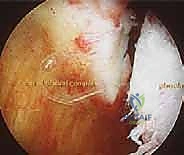

- رؤية بانورامية فائقة: كاميرا 4K تتيح للجراح رؤية تفاصيل المفصل الدقيقة التي لا يمكن رؤيتها بالعين المجردة في الجراحة المفتوحة.